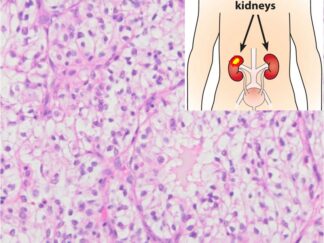

Human Kidney Cancer FFPE Sections